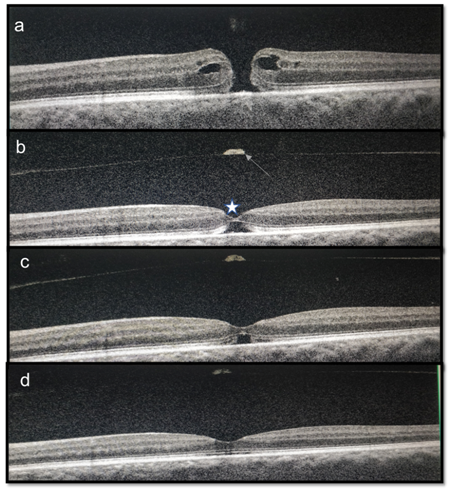

A 64-year-old female, presented with decreased vision in left eye, since 3 months. The visual acuity on Snellens chart was 20/30, N6 in right eye and 20/200 and N36 in left eye. Anterior segment examination showed both eyes with nuclear sclerosis of grade 3. The fundus of right eye was within normal limits with left eye optic disc and macula appeared normal (Figure1a &b). As vison was not correlating, optical coherence tomography (OCT) was done which revealed full thickness macular hole (FTMH) (Figure 2a). The dimensions of MH were, diameter of 286microns (m) and the basal dimeter of 486m. The patient was advised combined surgery but opted for only cataract extraction (phacoemulsification with a 2.8mm corneal incision) with single piece foldable intraocular lens implantation with no intraoperative complications. At 1 month follow up vision was 20/60, N24. OCT in left eye showed a separated vitreous with operculum with inner retinal layer apposition with outer lamellar hole (Figure 2b). At 2nd month, the inner retinal apposition increased, with decrease in outer lamella hole dimension (Figure 2c) and at 3rd month there was complete apposition of inner and outer retinal layers with final visual acuity of 20/40, N8 in left eye.

Figure 2 (a) OCT showing a full thickness macular hole. (b) At 1 month post cataract surgery inner retinal layer apposition (white star) is noted with outer lamellar hole with posterior hyaloid separation(white line). (c) OCT at 2nd month, there is increase in inner retinal layer apposition with decrease in the size of outer lamellar hole. (d) OCT at 3rd month showing complete spontaneous apposition of the inner to outer retinal layers.